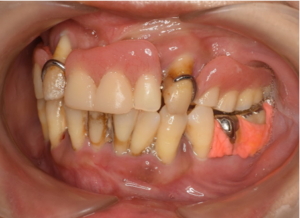

虫歯も歯周病も

一つの医院で対応できます

むし歯や歯周病を含めた治療計画を立てて治療するため、院内で総合的な対応が可能です。担当ドクターはむし歯・歯周病それぞれの学会に所属しております。